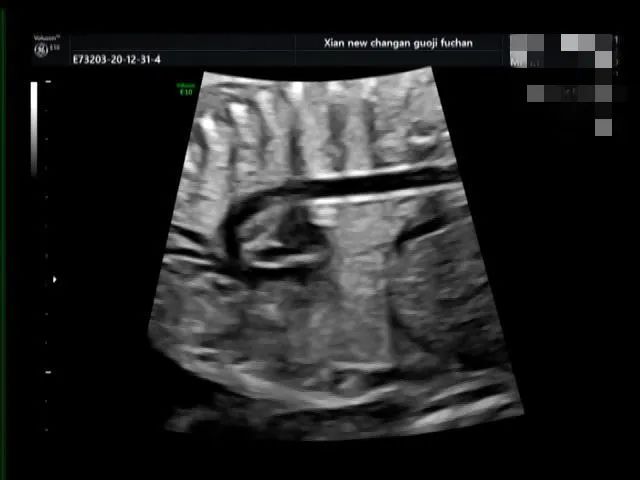

病例三

脐带打结

脐带打结是产科胎儿窒息的高危因素之一,利用产前超声检查能够提供准确有价值的诊断依据,我院自 2020 年 10 月至今共产前诊断处 4 例脐带打结。

产科医生向家属告知病情,因 4 例孕妇孕周都在 38W 以上,家属要求行剖宫产手术,娩出婴儿,Apgar 评分:10 分。外观无畸形,脐带中部近胎儿处见真性打结。

脐带真结较为少见,是脐带走形异常或脐带过长在宫内形成环套,胎儿活动穿越环套所致,往往引起不同程度的并发症,易引起胎儿宫内窘迫,严重者可致胎死宫内。

产前超声如怀疑脐带打结,需高度重视,孕期加强监护,注意可疑处脐动脉及脐静脉内径及血流动力学变化,3D 彩色多普勒高分辨仿真血流技术可立体、直观显示脐带形态结构及血流,对脐带打结有一定的诊断价值。